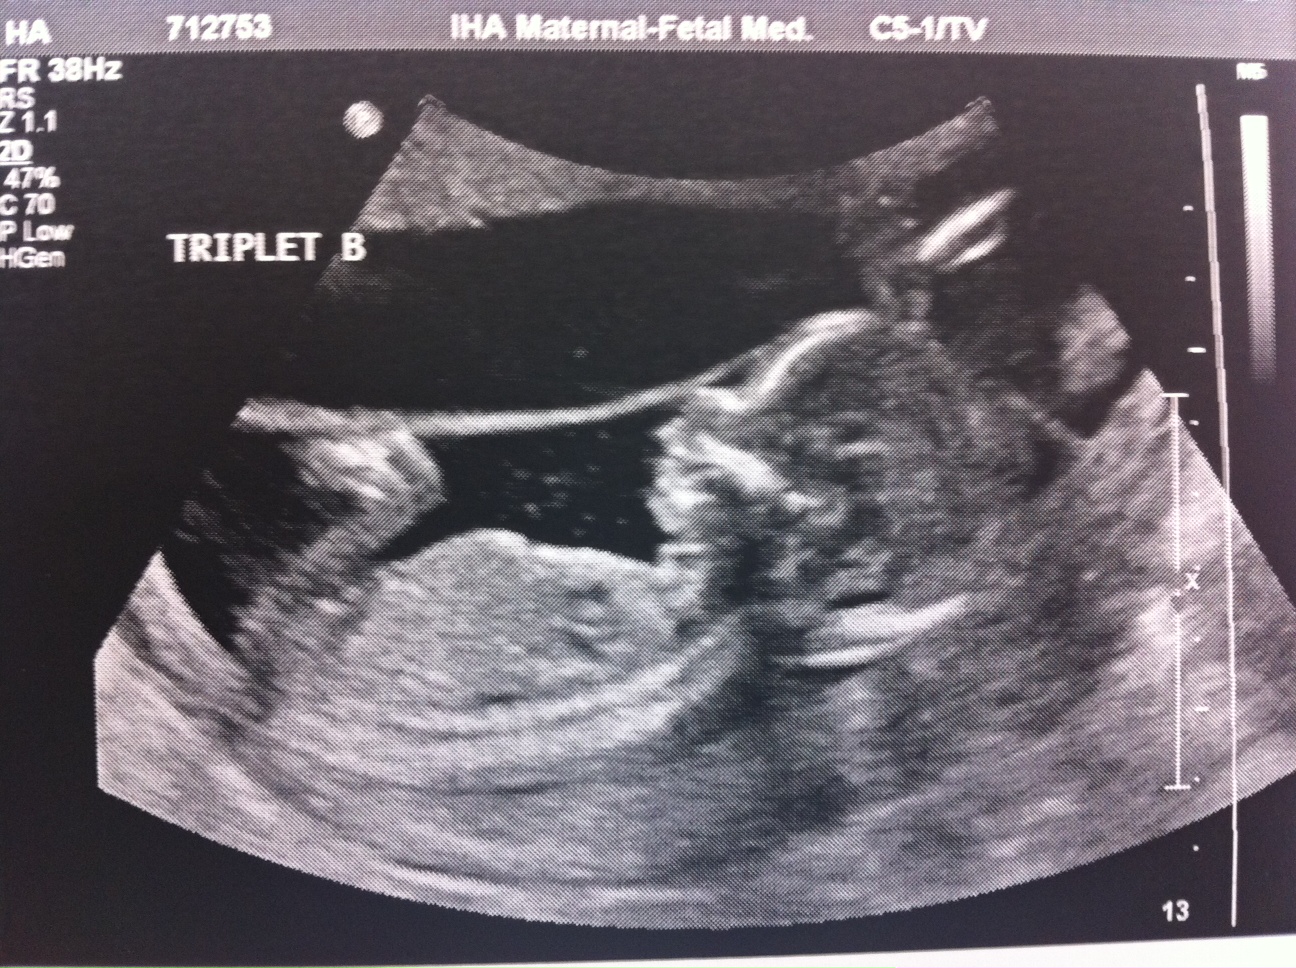

Baby B – is a GIRL!

A is 170 grams, B is 175 grams and C is 178 grams so they’re all measuring well. Grow, grow, grow!